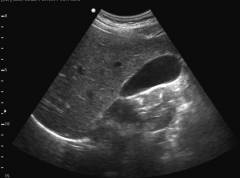

-

Ультразвуковое исследование. Во время него можно определить положение, размеры, толщину стенок желчного пузыря, наличие в нем камней и пр. - Прицельное биохимическое исследование крови – определение показателей, характеризующих функцию печени: АЛТ, АСТ, щелочная фосфатаза.